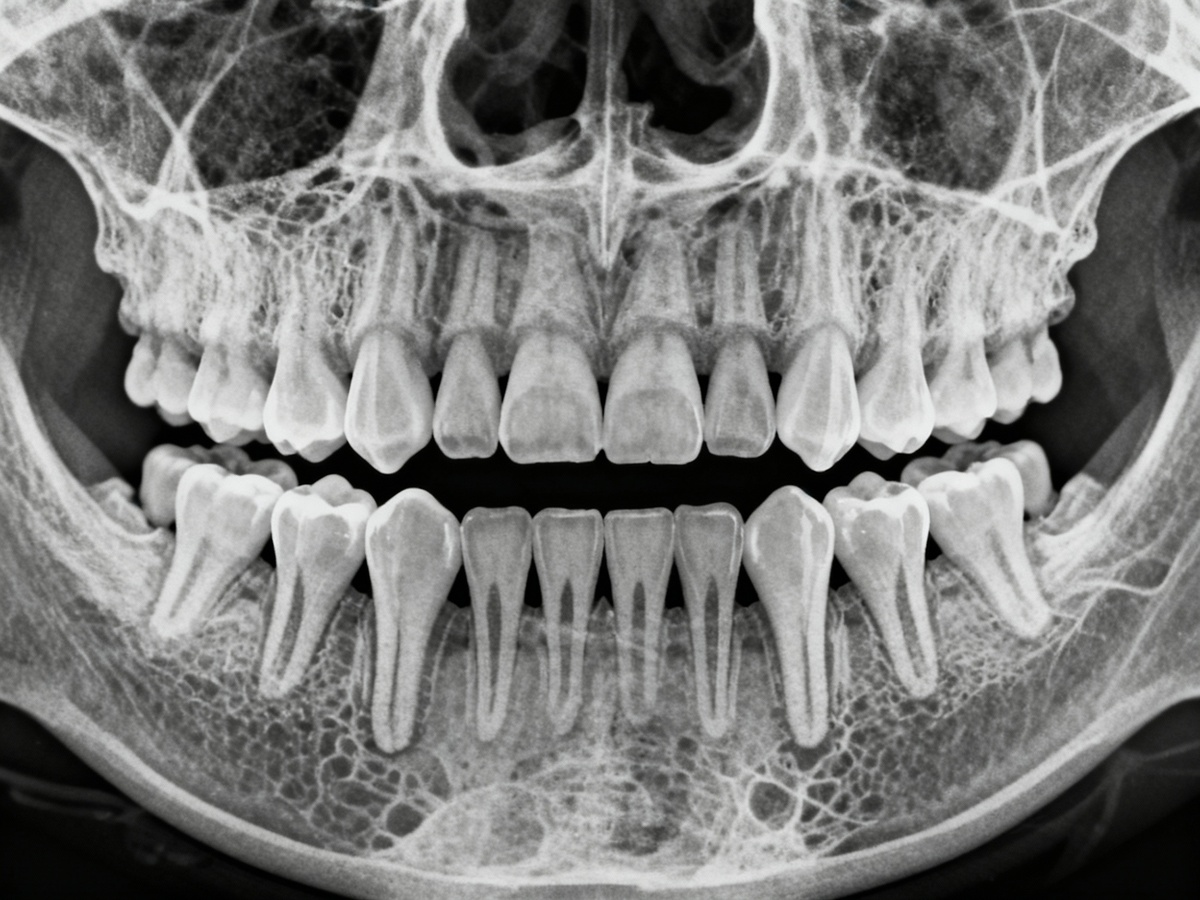

Рентгеновский снимок зубов мудрости: где они расположены в челюсти